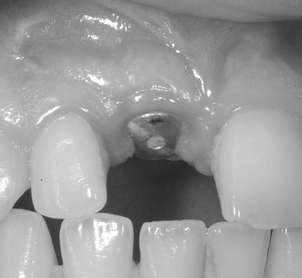

Photo du Dr Ramzi Redissi

Dans le cas où vous souhaiteriez réaliser la pose d’implants dentaires, votre médecin aura également besoin d’examens complémentaires tels qu’une radiographie et vous donnera rendez-vous pour une deuxième consultation afin de mieux pouvoir préparer l’intervention. A ce stade, il prendre des photos de votre bouche pour pouvoir comparer les résultats après votre intervention.